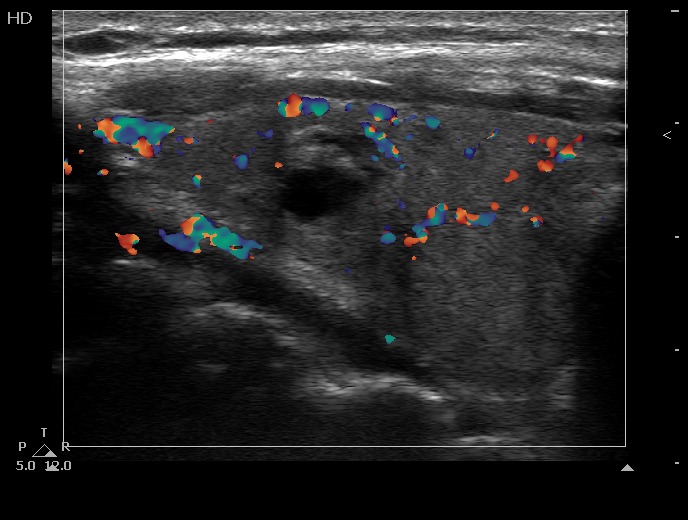

Ultrasonography. The thyroid was echonormal and contained several cystic areas and an echonormal nodule in the right lobe. There was a large, partly echonormal, partly hypoechogenic nodule in the left lobe. This lesion had irregular borders and presented an irregularly increased intranodular vascularization.